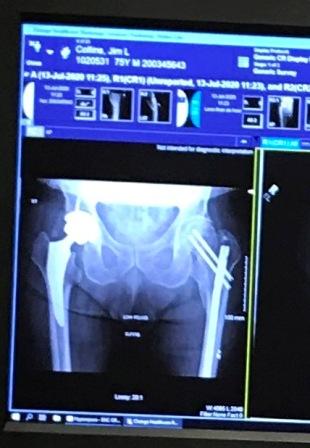

Jeff and Maggie welcomed me home after I was released from the hospital recovering from a broken wrist and hip. I learned my lesson to avoid climbing ladders. The x-rays show the damage and hardware to fix both hips. I broke the left hip in 2004 after crashing into a ski lift.